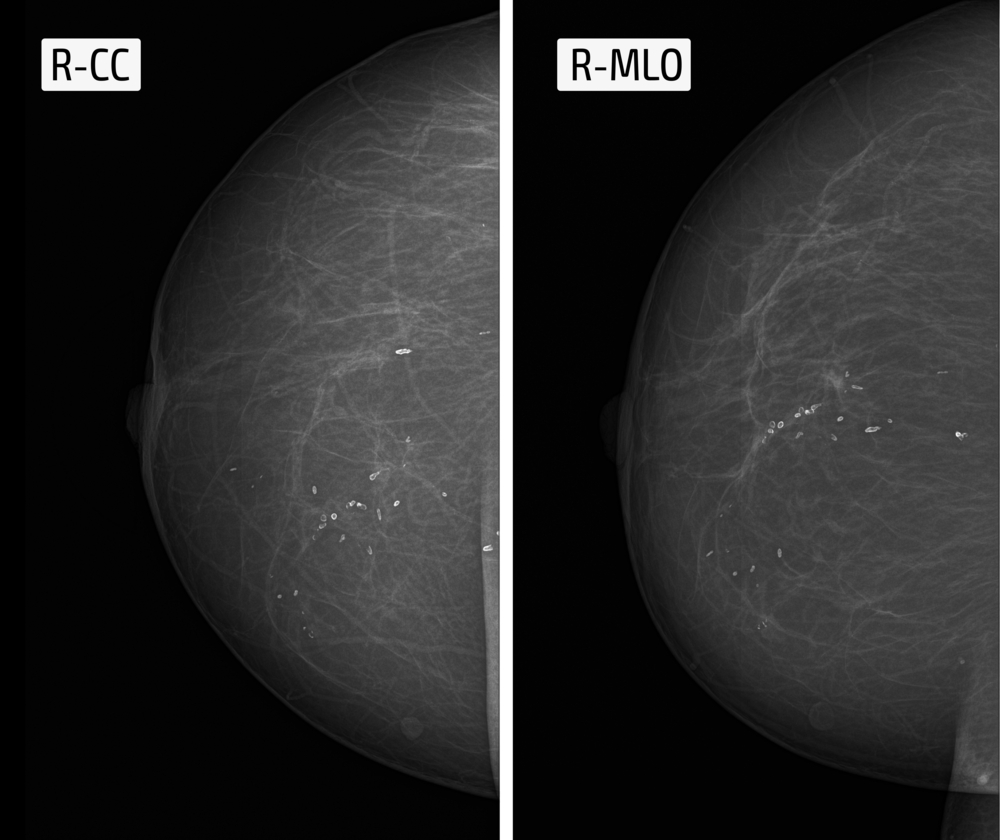

- маммография – данная методика позволяет выявлять кальцинаты, определять область их локализации, размеры, форму; кроме этого, снимки могут давать максимум информации о других патологиях груди, которые могли бы стать причиной появления очагов обызвествления (мастопатии, новообразований, кист и пр.);

Очаги обызвествления могут иметь различную форму, и нередко она предопределяется первопричиной формирования кальцинатов. Протоковые образования бывают точечными (прерывистыми), игольчатыми или червеобразными. Они более характерны для протокового рака. Дольковые образования обычно имеют форму полумесяца, осколков яичной скорлупы, а стромальные – в виде крупы, овала, попкорна или имеют бесформенные очертания.

В зависимости от размеров кальцинаты разделяют на микро- и макрокальцинаты. Микрообразования чаще обнаруживаются при злокачественных процессах, а макрокальцинаты – при доброкачественных. Однако этот признак не является диагностическим критерием, и ставить диагноз возможно только при проведении как минимум трех исследований, подтверждающих злокачественность процесса. К этим диагностическим методам относят: